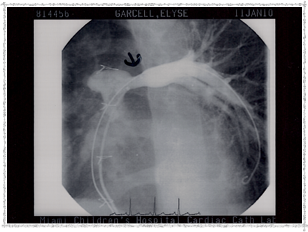

Second Catheterization — Dr. Danyal Khan

In 2010, Elyse underwent her second catheterization procedure, overseen by Dr. Danyal Khan at Miami Children's Hospital. The procedure focused on her pulmonary arteries, and these images show the before and after.

2010 - Left Pulmonary Artery Before

Left Pulmonary Artery — Before

2010 - Before Procedure

Before the procedure